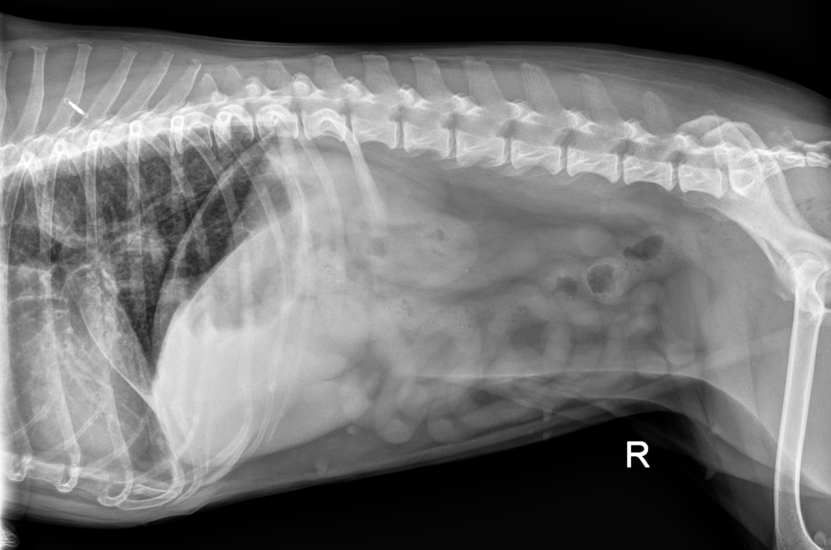

Thoracic findings:

- Moderate to marked tracheobronchial lymphadenomegaly (3cm soft tissue opacity caudodorsal to cardiac silhouette, at the carina)

- Bilateral mild to moderate pleural effusion (bilateral thick pleural fissures)

- Diffuse bronchial and peribronchial pattern, most marked in caudodorsal lung fields

- Cardiac silhouette at upper limit of size (3.5 intercostal spaces)

- Suspected right cardiomegaly, possibly cor pulmonale

Abdominal findings:

- Right renal silhouette caudally displaced with border effacement of adjacent hepatic silhouette

- Suspected right cranio-dorsal peritoneal/retroperitoneal mass (adrenal, lymphatic, or hepatic origin possible)

The diagnosis: The association of these findings was most consistent with neoplastic disease, lymphoma being the top differential, which could explain all thoracic findings and the GI signs. Chronic infectious bronchopneumopathy (particularly fungal) was also considered given the satellite lymphadenopathy.

Tracheobronchial lymphadenomegaly is one of the most commonly missed findings on thoracic radiographs. On lateral views, it's often obscured by the cardiac silhouette. On VD/DV views, it appears as a soft tissue opacity superimposed over the spine at the carina: exactly where many practitioners don't look closely. In Pepper's case, this 3cm mass was the key finding that shifted the entire diagnostic direction from "geriatric changes" to "systemic disease."